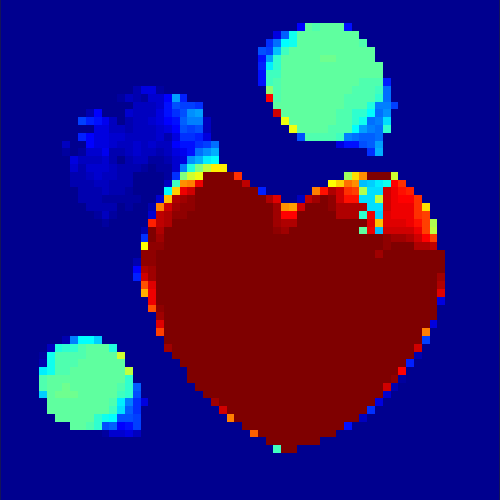

The first data set consists of a heart-shaped region and three circles on a static background (see figure 1 (a)). The two smaller circles are assumed to belong to

the same tissue type and therefore to the same subregion, which causes a total of four subregions, including the background. To simulate a more realistic application of dynamic SPECT

imaging, we used a synthesized representation of a rat liver as a second data set (see figure 1 (b)). The temporal concentration curves used to simulate the data sets

are shown in figure 2. As before, the total number of subregions was chosen to be equal to four in order to provide a both simple and realistic shape model.

In a first test, every image sequence was reconstructed out of the exact given sinograms. Additionally we tested noise corrupted data by first scaling the sinogram by a parameter , corrupting them with Poisson noise via the MATLAB imaging toolbox command imnoise and finally rescaling the image to the original range (see figure 4). The average count number per time step (i.e. the average of the discrete -norm of the data at each time step) is approximately in case of the heart-shaped data set and ca. in case of the rat liver simulation. The results at a certain number of time steps can be seen in figure 6 and 7. For comparison, we additionally performed a reconstruction with a simple alternating EM method, keeping the assumption that the tracer can be modelled as a sum of indicator functions and subconcentration curves, but neglecting any regularization terms. In all tests, the outer iteration number was set to 1000 with 10000 inner iterations per subproblem, to obtain a result within a reasonable time period. As stopping criterion, we chose the primal dual residual (cp. [12]) for the inner and the maximum over the Frobenius norms of and for the outer iterations. The results are displayed in 6 and 7 respectively.

As one can see in both figures, the reconstruction method applied to each data set performs very well, especially in contrast to the simple alternating EM method. This clearly shows the benefits of the proposed regularization methods. In case of noise-free given data, the shape of every object, where especially the heart is of higher interest, is clearly defined. As expected, we often observe errors in the edges of each region and where two regions are directly connected (the heart and the upper left circle). This causes the algorithm to incorrectly assign these pixels to another region. Furthermore, the reconstruction difficulties increase with an increase in noise. Some more pixels are assigned to the wrong region, which leads to a small hole-like structure within the heart region and causes a slight blurring effect. In the second data set the method clearly outperforms several other approaches by providing very clearly defined regions and even reconstructing fine structures of the phantom. However, as mentioned before, a clear reconstruction of the rat liver required highly optimized parameter sets, which makes the whole problem quite susceptible to parameter changes.